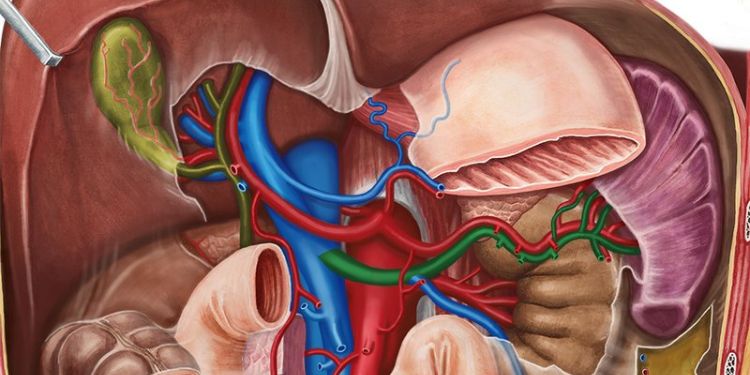

Journal of Spleen And Liver Research (JSLR) is a distinguished open access publication committed to disseminating pioneering research, reviews, and advancements in the domains of Pancreatic Cancer Endoscopy, Liver, Cirrhosis, Spleen, and Gastroenteritis. It serves as a vital platform for the exchange of cutting-edge knowledge and insights in these critical areas of medical science.

Journal of Spleen and Liver Research aims to provide a platform for the dissemination of high-quality research related to the anatomy, physiology, pathology, and clinical aspects of the spleen and liver. The journal welcomes original research articles, reviews, case reports that contribute to the understanding of spleen and liver biology, pathology, and clinical management.